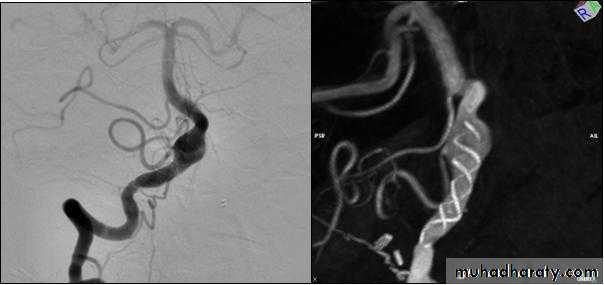

Angiography of buerger disease ((corkscrew))

Shape of aneurysmAngiography of cerebral aneurysm